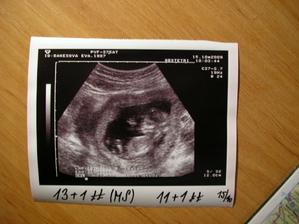

4.11. : 14+0tt (dle MS 16+0tt) Výsledky z genetiky jsou v pořádku a v poradně proběhlo jen vyšetření čípku - je dlouhý a tvrdý, takže také naprosto v pořádku